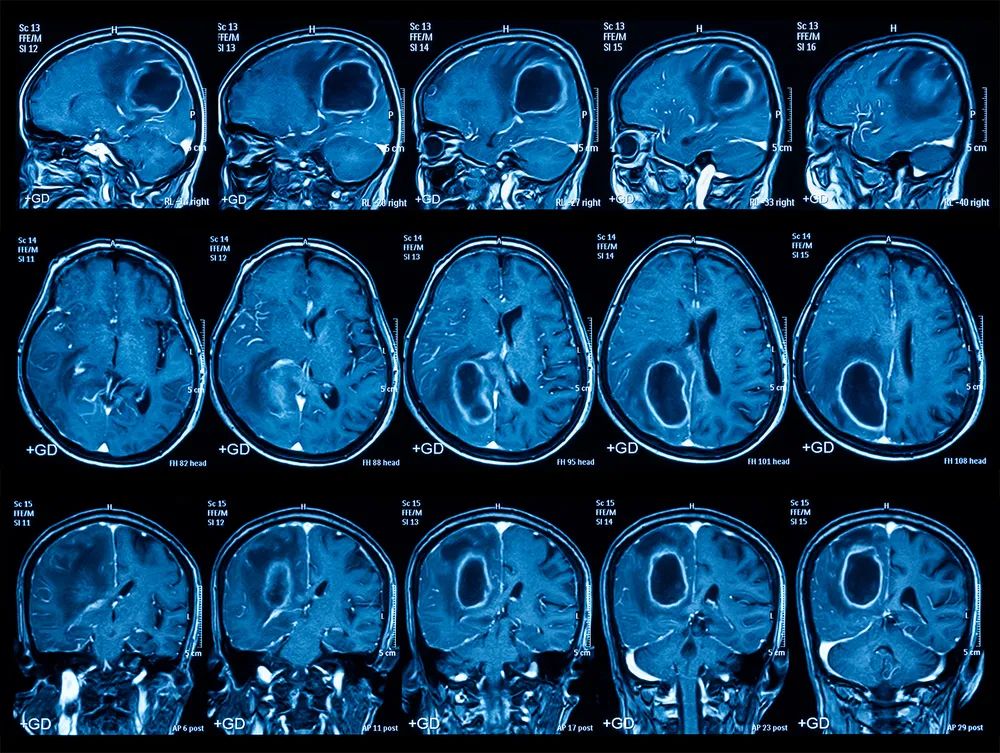

3. 核磁共振(MRI):让器官组织「自报家门」

脑灰质、白质密度十分相近,却可以在 MRI 成像中对比鲜明,也能非常清晰地显示脑肿瘤。正因如此,MRI 通常是神经系统疾病的最佳选择。

图片来源:giphy.com

图片来源:站酷海洛

当然了,这只是 MRI 成像原理的最简单解释,它还有不同的不同的成像参数和成像序列图像,对应的含义也大不相同。一个会看 MRI 的医生,需要大量的经验积累和知识储备,一定没少为此头秃。